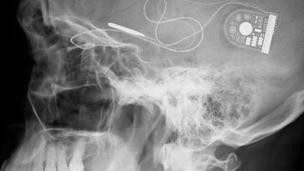

آنها تراشه میکروالکترونیک سه میلی متر مربعی را که در برابر نور بسیار حساس است و به جای دریافت کننده های نور عمل می کند را در سر این دو مرد نابینا توسط یک عمل جراحی پیوند کردهاند.

در این عمل جراحی تراشهای پشت شبکیه چشم گذاشته شد و سیمی از آن از زیر پوست به پشت گوش وصل شد.